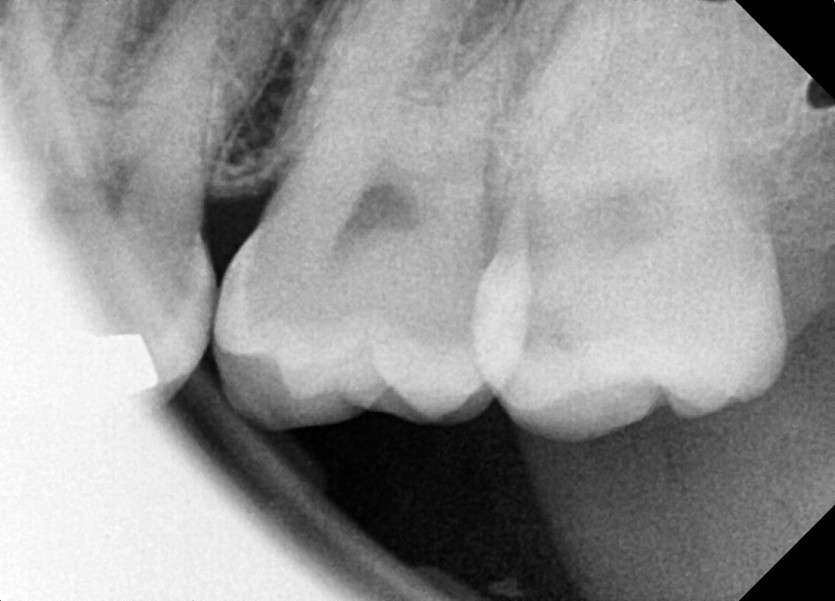

#28,38 사랑니 발치

구강 외과 전문의가 당일 발치했습니다.